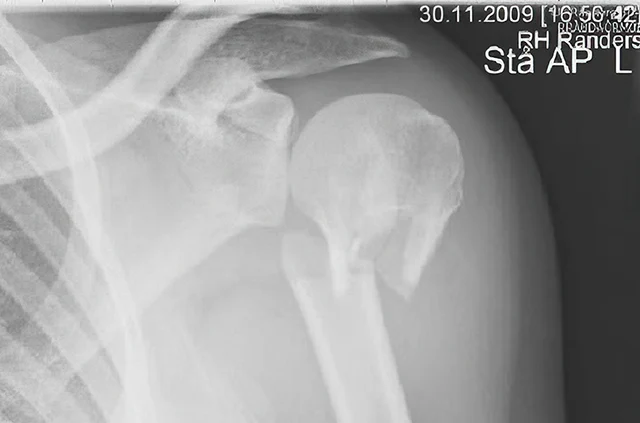

Prelom gornjeg dela nadlaktice

Prelom gornjeg dela nadlaktice javlja se najčešće kod starije populacije (preko 65 godina). Ukoliko je u pitanju prost prelom nadlaktice (tzv. dvodelni prelom nadlaktice) i ukoliko je položaj koštanih fragmenata zadovoljavajući, lečenje je konzervativno – trouglom maramom. Ukoliko je prelom nadlaktice iz više fragmenata, oni su često pomereni (dislocirani) i tada se preporučuje hirurška intervencija. Najčešće se pod pojmom preloma ramena podrazumeva ovaj prelom.

Prelom gornjeg okrajka nadlaktice (humerusa), rendgenski snimak

Prelom humerusa